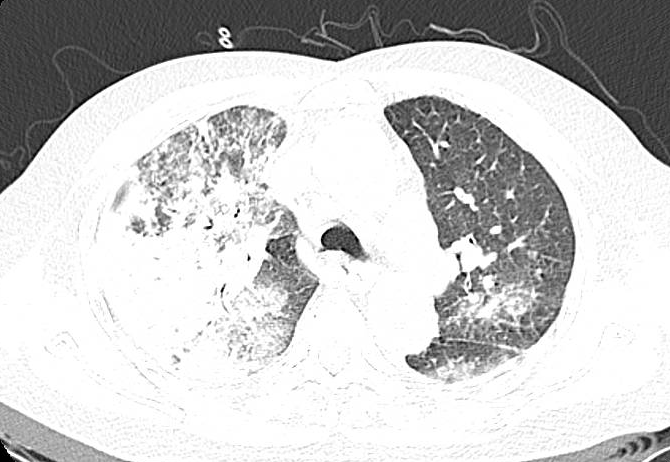

这两位患者症状相似:68岁的黎阿姨(化名)因饲养家鹅后突发高热、干咳,胸部CT显示双肺大面积感染,右肺几乎呈“白肺”;50岁的刘大哥(化名)因从事饲料批发工作常接触鸡群,同样出现不明原因的超高热,影像学也呈现典型的“白肺”表现。两位患者均因高热难退转入广医附属番禺中心医院。

接诊医生通过重点追问禽类接触史这一关键环节,迅速将诊断方向锁定为“鹦鹉热衣原体肺炎”。随后,通过气管镜肺泡灌洗检查和检测结果显示二人为鹦鹉热衣原体感染。

经针对性抗感染治疗,黎阿姨与刘大哥分别在用药后第3天和第2天体温恢复正常,并先后康复出院。这两个病例清晰地证明,对于突发高热伴快速进展肺炎的患者,详尽的环境与职业暴露史问诊是避免误诊、实现精准早期治疗的决定性一步。